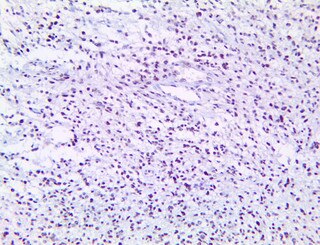

IgG1 - BSB-169